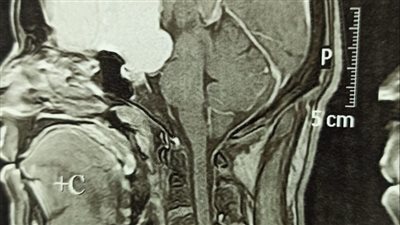

علاج 861 حالة بوحدة الأشعة التداخلية بمستشفى جامعة سوهاج

إستئصال ورم لشاب عشريني بسوهاج الجامعي ينقذه من فقدان البصر

إجراء 4 عمليات جراحية في العيون لمصابي غزة بمستشفى جامعة سوهاج